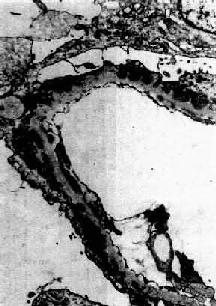

膜性肾小球肾炎

电镜下见肾小球毛细血管基底膜增厚,电子致密沉积物被增生的基底膜包围并埋藏于基底膜内